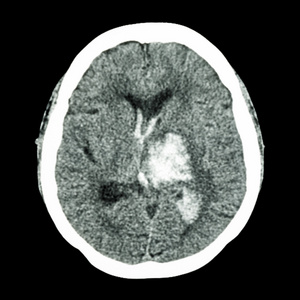

脑出血的部位 (1)壳核出血 (2)丘脑出血 最常见,约占 脑出血的60% ~65

图片尺寸1080x810![丘脑出血所致的眼偏斜反应1例 [病例帖]](https://i.ecywang.com/upload/1/img0.baidu.com/it/u=1823881664,1347455832&fm=253&fmt=auto&app=138&f=JPG?w=889&h=500)